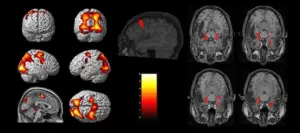

دومین دوره آموزشی تصویربرداری و آنالیز داده های تصویربرداری تشدید مغناطیسی عملکردی (fMRI)

-مبانی تصویربرداری و مقدمه ای بر آنالیز تصاویر fMRI

- تصویربرداری کارکردی تشدید مغناطیسی وابسته به Task و در حال استراحت

- کنتراست BOLD و منشا فیزیولوژیکی آن

- کاربردهای fMRI در Presurgical Planning و سایر کاربردهای آن

Functional MRI (fMRI)

-اصول پردازش تصاویر fMRI

- آشنایی با اصول پایه ای تصویربرداری fMRI

- روشهای پیشپردازش و پردازش دادههای fMIR

Functional MRI (fMRI) of the brain

Functional magnetic resonance imaging (fMRI)

-پردازش تصاویر fMRI (کار با نرم افزار)

- معرفی و نحوه کار با تولباکس CONN

- معرفی و نحوه کار با نرم افزار FSL